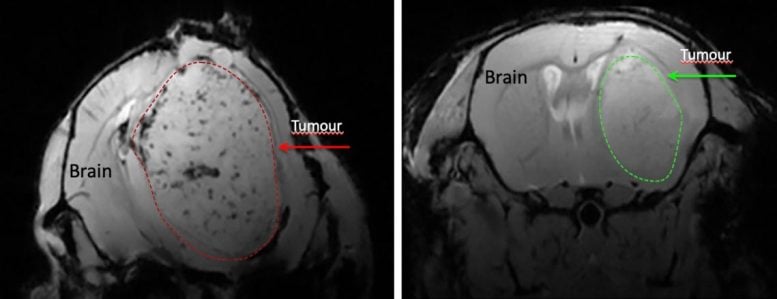

“Il medico mi ha detto che avevo una massa nel cervello e che dovevo farmi visitare da un oncologo”, racconta Waldner.

La diagnosi è stata di glioblastoma, una delle forme più aggressive di tumore cerebrale. Il trattamento standard prevede in genere tre fasi: intervento chirurgico per rimuovere la maggior parte possibile del tumore, seguito da radioterapia e chemioterapia. Nonostante decenni di ricerca e progressi in oncologia, la malattia si ripresenta quasi sempre.

La ricerca è iniziata con esperimenti di laboratorio sui topi, nei quali è stato dimostrato che la niacina prolunga la sopravvivenza. Questi risultati hanno gettato le basi per una sperimentazione clinica di fase I e II sui pazienti.

I ricercatori hanno fissato un parametro di riferimento: lo studio sarebbe proseguito solo se la sopravvivenza libera da progressione a sei mesi fosse migliorata di almeno il 20% rispetto ai dati storici. I primi risultati su 24 pazienti hanno mostrato che l’82% non ha presentato progressione della malattia a sei mesi.

Ciò rappresenta un miglioramento del 28% rispetto agli studi precedenti, suggerendo un potenziale beneficio in un tumore che rimane difficile da trattare.